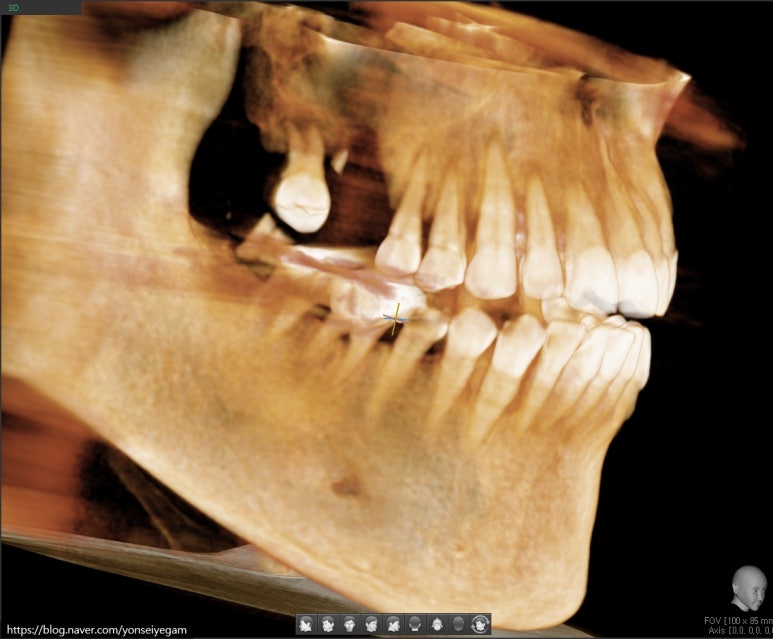

오랜 시간 치아가 방치되어 아래 파노라마와 같은 모습이었습니다.

큰 위쪽 어금니는 3개가 없고 하나는 매우 흔들리는 상태,

아래쪽 큰 어금니는 파절되고 썩어있는 상태였습니다.

엑스레이 사진에서 길이측정을 해보면 위쪽 어금니쪽에 뼈 수직길이가 2~3 미리 정도밖에 남지 않아

보통 심는 8~10미리의 임플란트를 심기위해 상악동수술(상악동거상술과 뼈이식)도 해야하는 상태였습니다.

정확한 임플란트 식립을 위해 3차원 ct를 사용합니다.

3차원 CT로 임플란트를 심을 위치를 3차원적으로 분석한 후 임플란트를 심습니다.